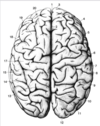

Key gyri on superior view of frontal cortex

Superior frontal gyrus

Middle frontal gyrus

Inferior frontal gyrus

Precentral gyrus

Key sulci on superior view of frontal lobe

Superior frontal sulcus

Inferior frontal sulcus

Precentral sulcus